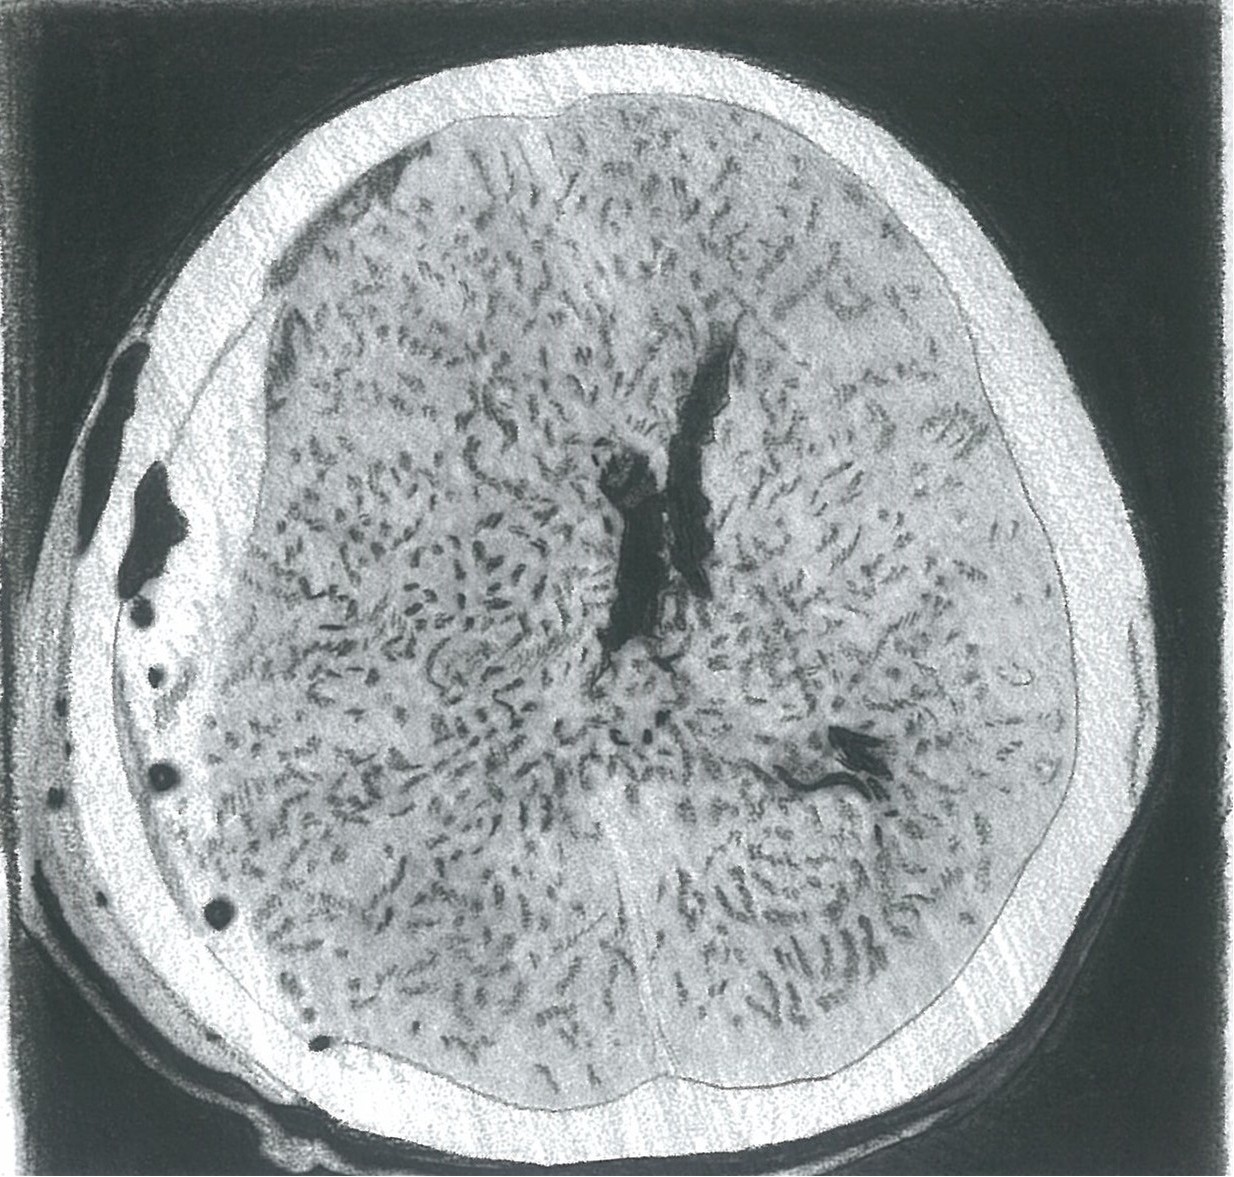

芝罘区的王先生今年60岁,前段时间他感觉左侧手脚活动无力,且不断加重,自认为是“脑血栓”,便服用阿司匹林,用以疏通血管。用药一段时间后,病情非但不见好转,反而愈发严重,除了肢体无力,走路也不稳了,最后他选择到烟台山医院北院神经外科就诊。夏广文主任仔细询问病史后得知,王先生曾在两个月前不小心头磕到了门框上,结合病情分析,高度怀疑存在颅内慢性出血的可能性,颅脑CT检查显示:“右侧额颞顶部位颅板下可见新月形稍高密度影,右侧侧脑室受压移位,中线结构左侧移位”,这也进一步证实了夏广文主任的判断,而且当时已经有了脑疝的征象,如果再拖延下去,会有生命危险。.

图A、B、C术前颅脑CT示:右侧额颞顶部位颅板下可见新月形稍高密度影,右侧侧脑室受压移位,中线结构左侧移位。

图D、E、F复查颅脑CT:硬膜下血肿清除完全,无二次出血等副损伤,中线结构回归,脑室受压解除。

夏广文主任团队紧急为王先生实施了慢性硬膜下血肿钻孔引流术。术后,原本肢体无力情况很快得到缓解。复查颅脑CT,颅内血肿清除完全,无二次出血等并发症的发生,出院时也未遗留肢体运动障碍。